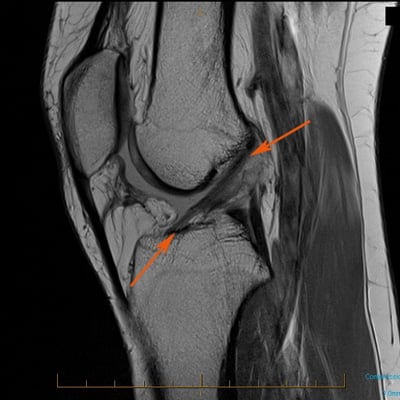

Клинически воспаление связок проявляется тупой болью, скованностью, хрустом при сгибании и разгибании колена. Эти симптомы неспецифические, то есть могут указывать на многие заболевания коленного сустава. Что касается рентгенографии, она также малоинформативна в диагностике лигаментита.

Понять, что у человека повреждены именно связки, можно лишь с помощью УЗИ или МРТ. Более специфические симптомы имеет лигаментит связки надколенника. Поскольку заболевание широко распространено среди спортсменов, его еще называют «коленом прыгуна».